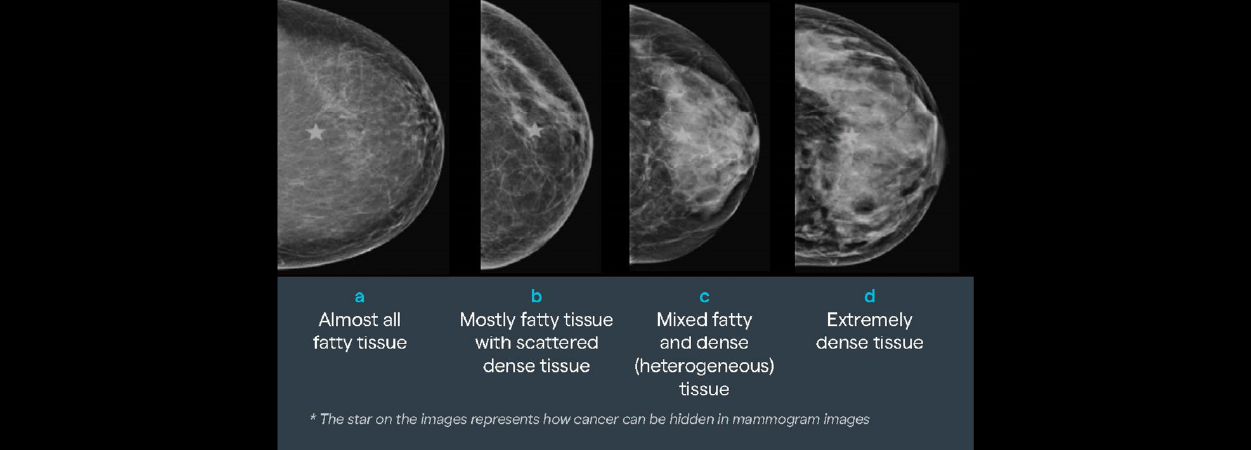

Breast cancer is the most frequently diagnosed cancer among women in Europe. Dense breast tissue, present in around 40–50% of women undergoing mammographic screening, both reduces the sensitivity of full-field digital mammography and independently increases the risk of developing breast cancer. While supplemental imaging can improve cancer detection in women with dense breasts, clinical practice, guideline implementation, and professional awareness vary greatly across European countries. This doctoral study sought to address these disparities and inform best practice through a multi-phase, mixed-methods approach conducted in four sequential phases.